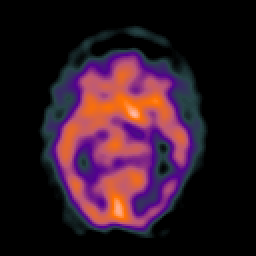

SPECT TC Study #1 -- Slice #24

[Home][Help][Clinical][Tour 1][Tour 2][Tour 3] Slice 24